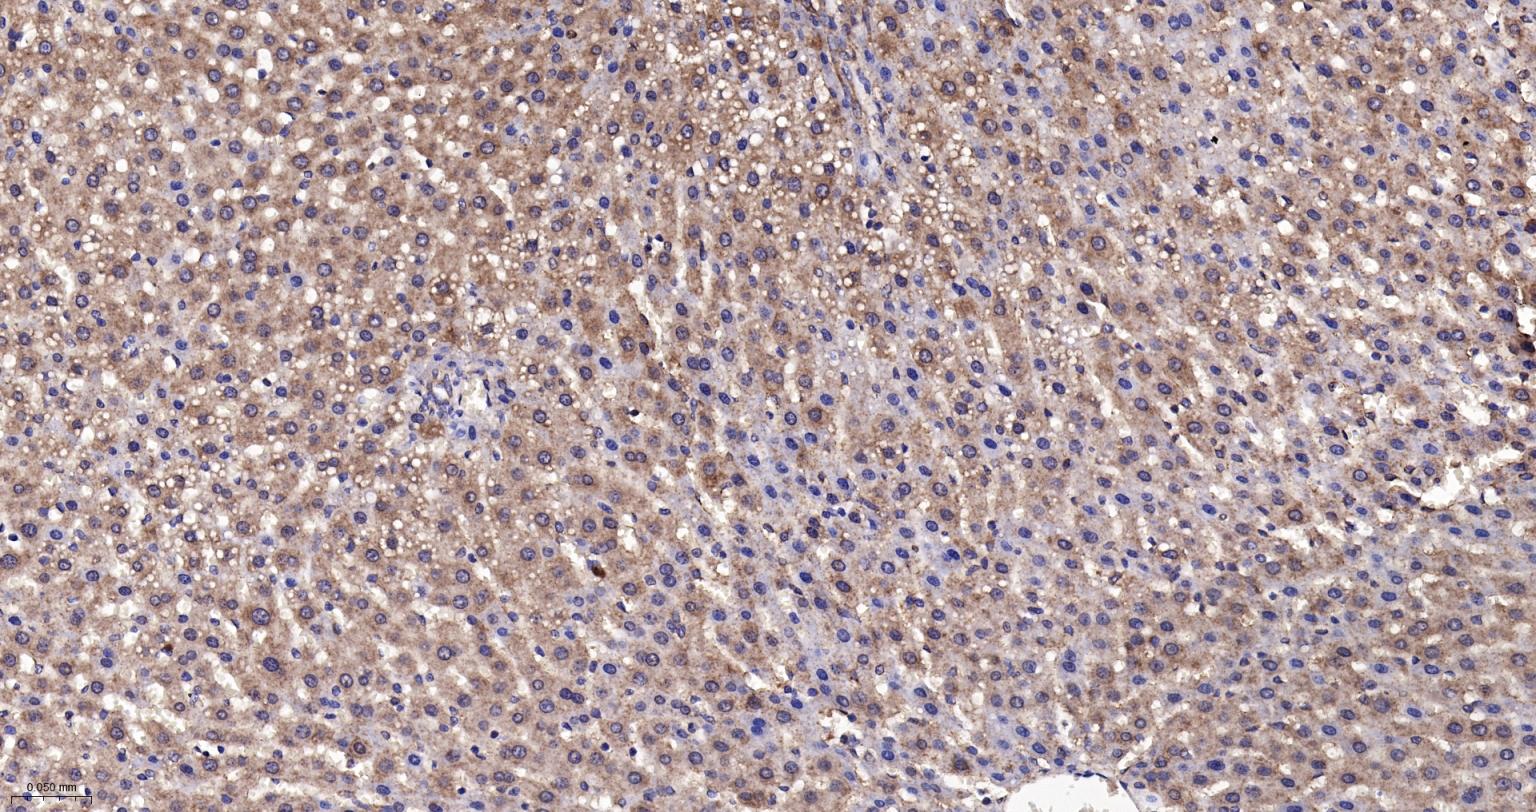

Paraformaldehyde-fixed, paraffin embedded Rat Liver; Antigen retrieval by boiling in sodium citrate buffer (pH6.0) for 15 min; The section was incubated with Annexin A7 Monoclonal Antibody, Unconjugated (bsm-61169R) at 1:200 overnight at 4°C, followed by conjugation to the bs-0295G-HRP and DAB (C-0010) staining.

Paraformaldehyde-fixed, paraffin embedded Mouse Liver; Antigen retrieval by boiling in sodium citrate buffer (pH6.0) for 15 min; The section was incubated with Annexin A7 Monoclonal Antibody, Unconjugated (bsm-61169R) at 1:200 overnight at 4°C, followed by conjugation to the bs-0295G-HRP and DAB (C-0010) staining.